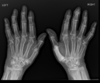

Espondilite anquilosante

Homens jovens, 3 década

Sacroileíte bilateral e simétrica

Coluna: Shiny corners (romanus): erosões nos cantos vertebrais com esclerose reativa;

vértebra quadrada (perda da concavidade anterior); espondilodiscite não infecciosa (lesão de andersson); aparência em bambu (anquilose dos sindesmófitos); sinal da faca (ossificação central - ligamento interespinhoso no rx ap),